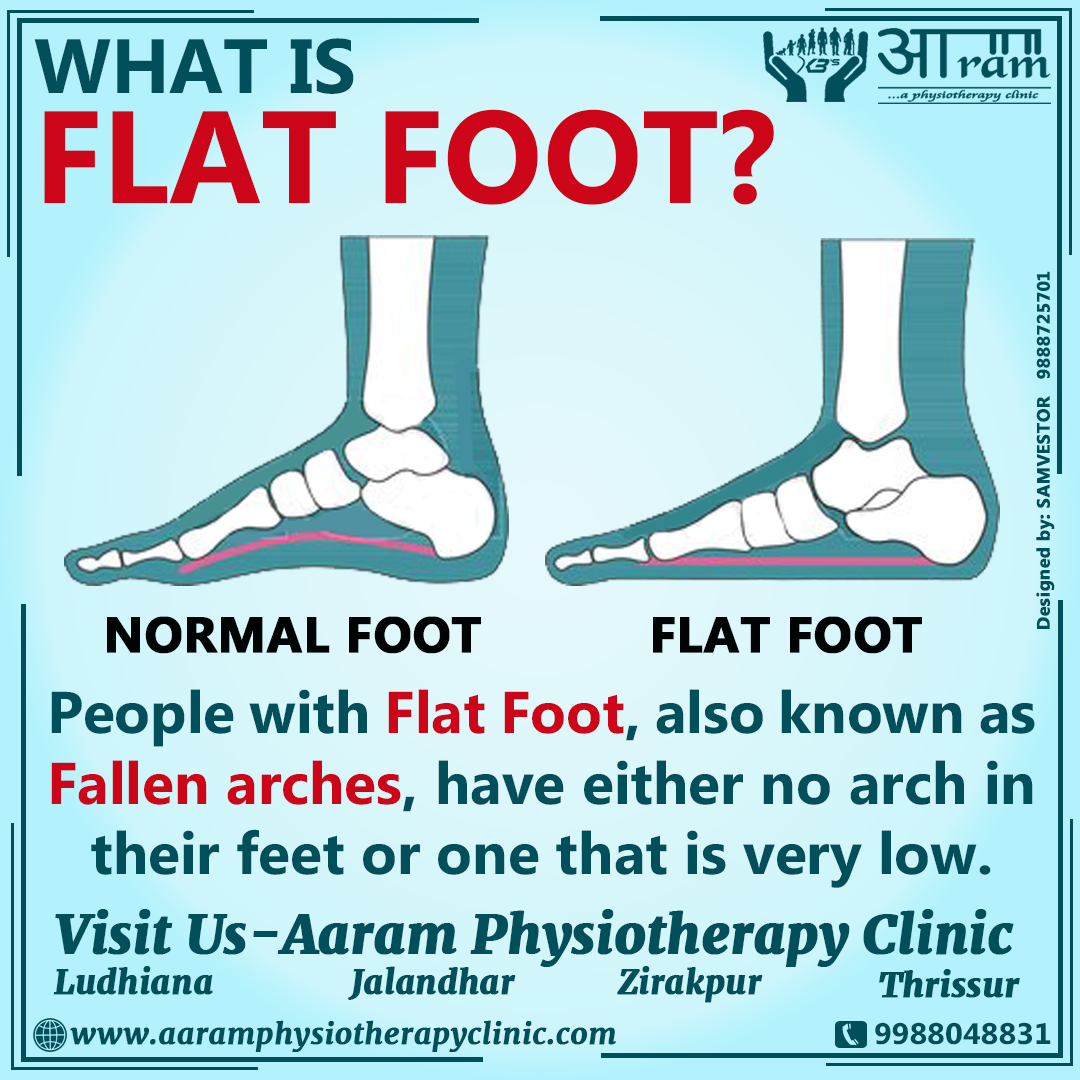

pictures of flat feet

FLAT FOOT- Definition, Symptoms, Causes & Rehabilitation Exercises

Flat Foot: Symptoms, Causes And Treatment Of Pes Planus